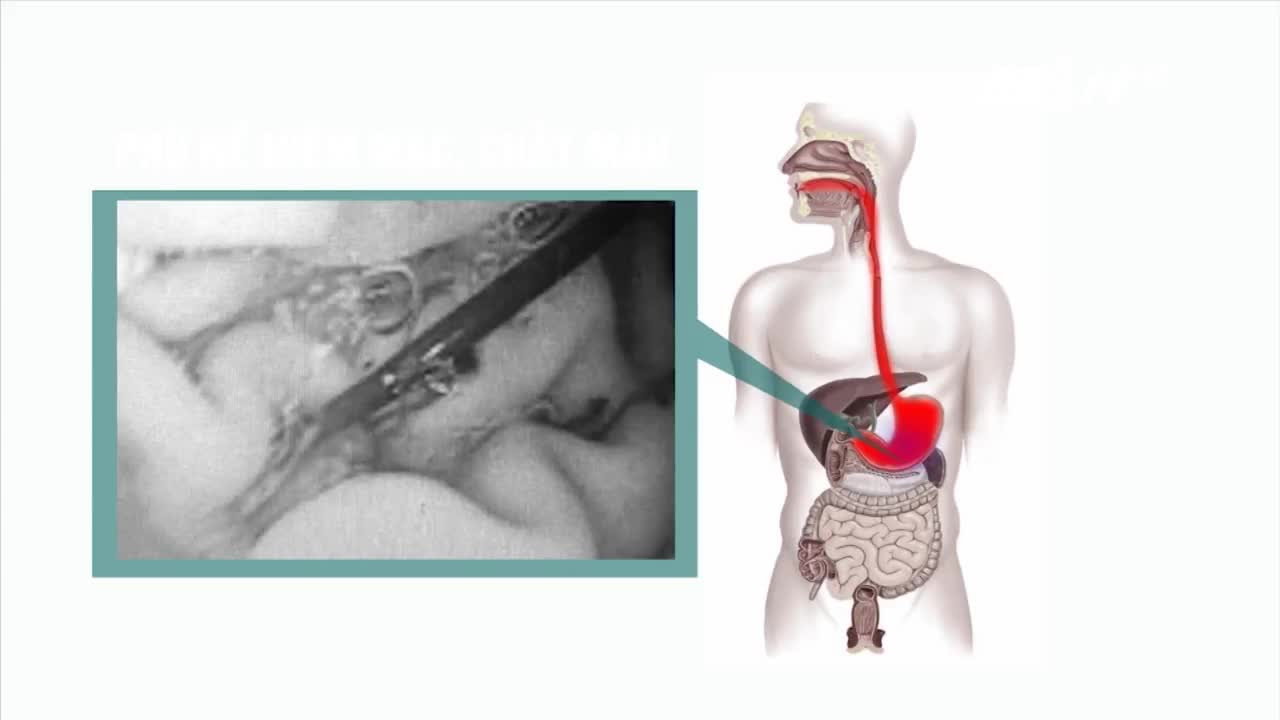

Tuy nhiên, sau khi xúc xích bị tiêu hóa hết, 2 thanh sắt đã đâm xuyên thành dạ dày của học viên này.

Mới đây, một học viên cai nghiện ở TP.HCM bẻ 2 thanh sắt của khung lồng quạt máy ở trong trại, sau đó cho 2 cây sắt này vào xúc xích để ăn nhằm được đưa đi cấp cứu rồi trốn thoát ở bệnh viện.